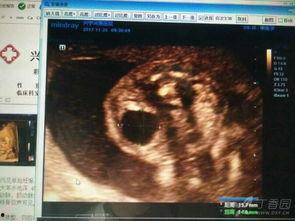

在怀孕23周的时候,宝宝已经长到了大约28厘米,体重大约有400克左右。这时候的宝宝,皮肤开始变得红润,头发也开始长出来,虽然还不是很明显,但已经能看出宝宝的五官轮廓了。

1. 视频中,医生通过超声波展示了宝宝在妈妈肚子里的样子,可以看到宝宝的头部、身体、四肢都十分清晰。